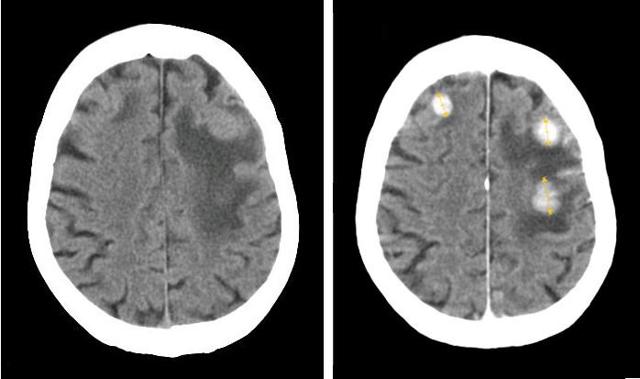

Image Source: Diffusion Pharmaceuticals Inc. | Technology Overview

Image Source: Diffusion Pharmaceuticals Inc. | Overview / Trans Sodium Crocetinate (NASDAQ:TSC)